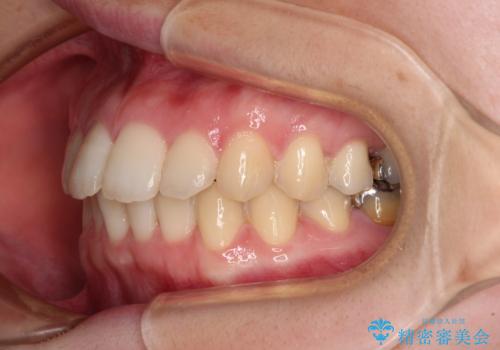

デコボコ歯列をきれいに インビザラインによる矯正治療

- 上下歯列全体のデコボコを気にして来院された患者様です。

主に下顎歯列全体の後方移動とIPR(歯と歯の間を削る)によってデコボコが解消するように設計し、インビザラインにより治療を行うこととしました。

1年半程度で終了するのではないかと予想しましたが、途中1年以上の来院がなく、トータルで3年の時間がかかってしまいました。

前歯のデコボコはより改善することが望ましい状態でしたが、患者様の希望により終了することとなりました。